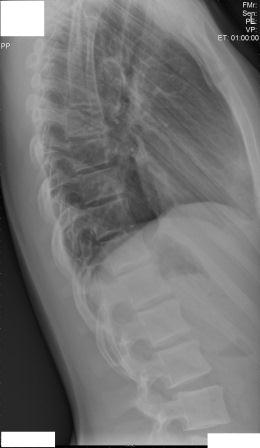

Hier sind alle Röntgenbilder.

Ist es jetzt anhand diesen Bildern nötig, zu einem Osteopathen zu gehen oder nicht?

- rückenansicht 1.jpg (11.74 KiB) 7115 mal betrachtet

- seitenansicht 1.jpg (16.39 KiB) 7115 mal betrachtet

- seitenansicht 2.jpg (12.07 KiB) 7115 mal betrachtet

Es ist in jedem Fall erforderlich !

Gerade bei einer 13-jährigen !

Ein Hohlkreuz ist zu sehen, der Rundrücken ist aufgrund der fehlenden Seitenansicht 3 nicht richtig einzuschätzen.

Die Skoliose im LWS Bereich (ich kann den Grad nicht abschätzen, oberer Bereich fehlt) sollte auf jeden Fall angegangen werden.

Ich habe den COB Winkel Lumbal ausgemessen, allerdings nur auf dem Bildschirm und komme auf ca 9° Lumbal. Eine deutliche Rotation erkenne ich nicht.

Auf dem frontalen RTG Bild ist zu sehen, dass das Becken nicht ganz gerade ist. Somit ist es möglich, dass Linkes Bein etwas kürzer ist als das Rechte und somit eine Statische Skoliose vorliegt, da die Statische Skoliose in Richtung des Verkürzten Beines geht und das ist auch hier der fall, die Verkrümmung Lumbal geht nach links.

Es währe sicher sinnvoll deine Schwester einem Orthopäden vorzustellen und bei der nächsten RTG Kontrolle, falls nötig die Beinlänge Ausgleichen.